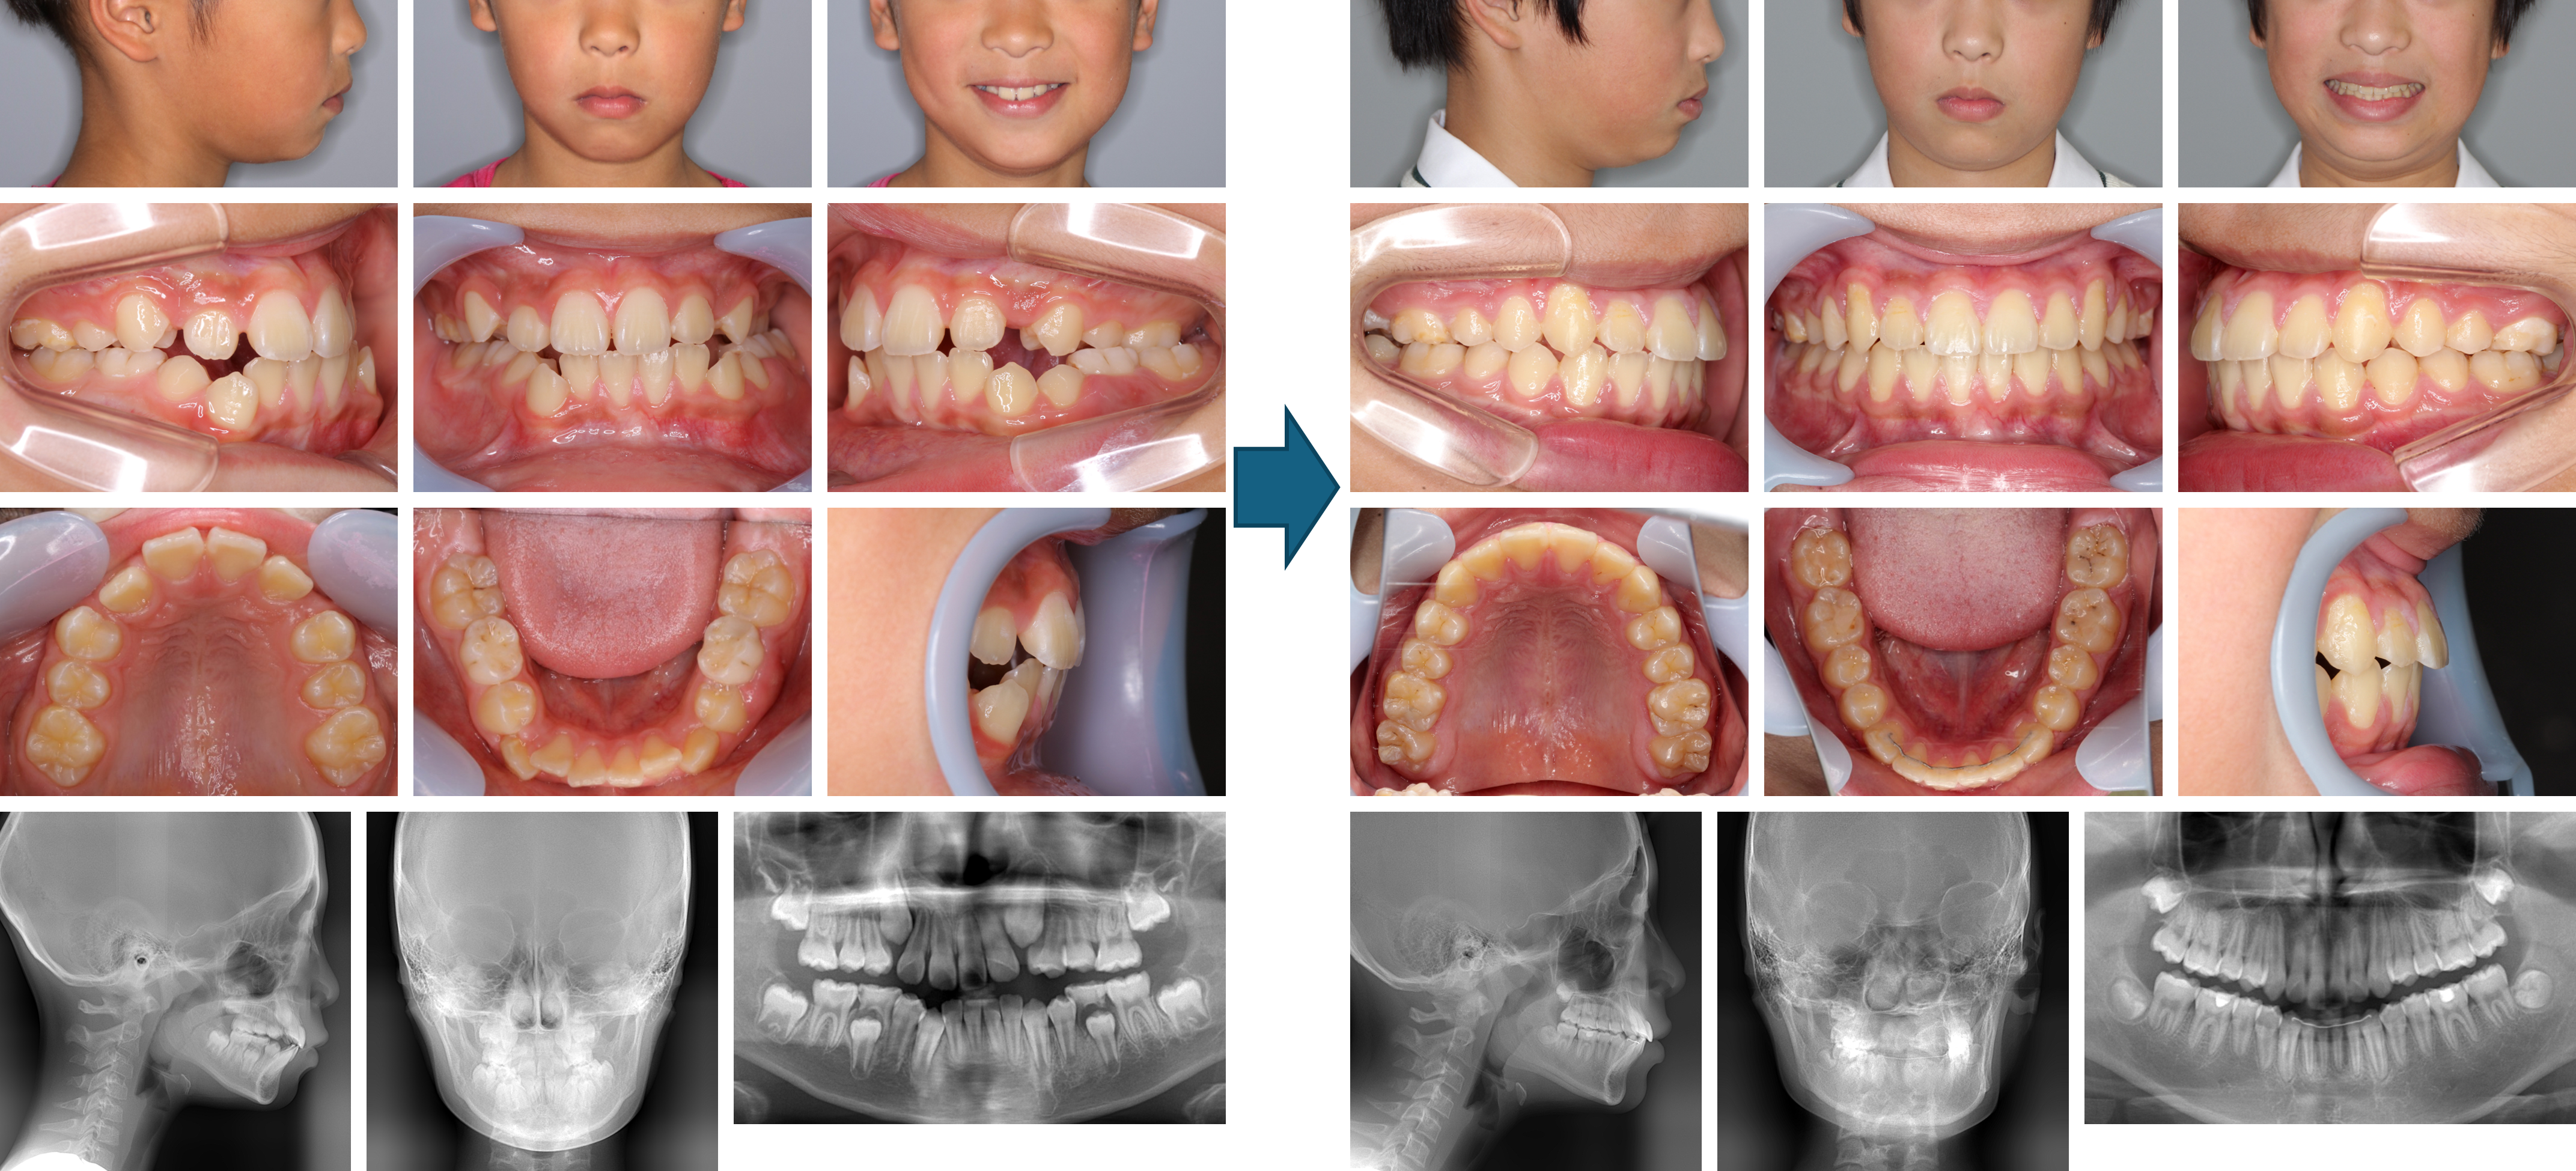

【治療例 K7482】初診時年齢:7歳3か月 / 性別:男性 / 主訴:不正咬合、受け口、すきっ歯

症例の概要:本症例は、受け口を主訴に他院から紹介され来院された。顔面写真より下唇が突出したコンケイブタイプで前歯部の交叉咬合の他、上顎両側第二乳臼歯の早期脱落および崩壊に伴って上顎両側第一大臼歯は第一乳臼歯に隣接していた。夜間にチンキャップを装着してもらい、上顎にはエクステンションリンガルアーチで上顎両側第一大臼歯の歯冠の遠心移動を図りつつ、上顎前方拡大床で上顎前歯部を唇側へ傾斜移動させようとしたが上手くいかなかった。装置をアクチバトールに変更したところ、反対咬合は改善された。マルチブラケット装置にて上顎両側第二小臼歯の萌出スペースの獲得を得られず、上顎両側第一小臼歯を抜歯した。結果的には整った顔貌と綺麗な咬み合わせになった。現在下顎両側第二大臼歯の萌出を待っている。

主訴:不正咬合、受け口、すきっ歯

診断名:上顎両側第一大臼歯の異所萌出を認めた前歯部交叉咬合の骨格性下顎前突

使用した主な装置:チンキャップ、エクステンションリンガルアーチ、上顎前方拡大床、アクチバトール、マルチブラケット装置

抜歯/非抜歯および抜歯部位:抜歯(上顎両側第一小臼歯)

治療期間:3年2か月

治療回数:51回